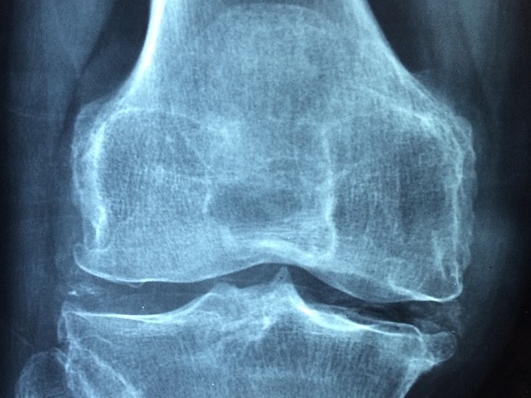

① 콘드로이친 효능 첫번째는 골 관절염 통증 감소 효과입니다. 골 관절염은 우리 몸의 뼈와 뼈 사이에서 완충 작용을 하는 연골이 닳아서 생기는 질환입니다. 콘드로이친을 장기 복용하면 골 관절염 통증 감소에 효과가 있다는 연구결과를 쉽게 찾아볼 수 있습니다.

② 콘드로이친 효능 두번째는 프로테오클리칸의 생성을 활발히 해주는 효과입니다. 프로테오클리칸은 연골이 닳으면서 관절의 간격이 좁아지는 것을 방지해주는 성분으로 콘드로이친을 복용했을 때 활발히 생성된다고 합니다.